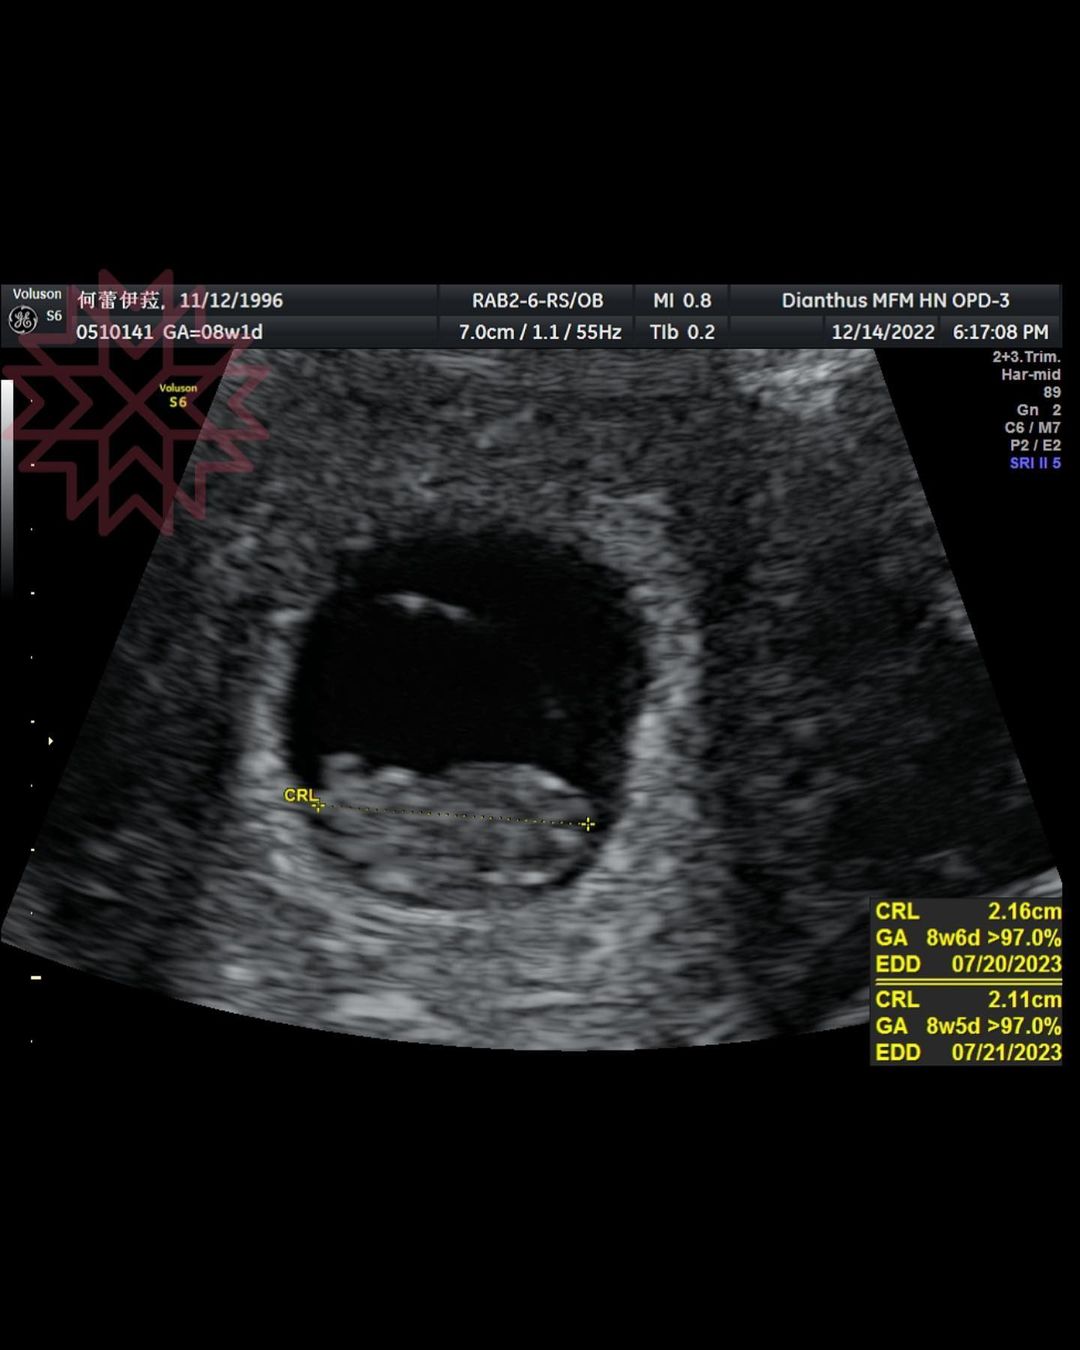

蕾菈22日在IG驚喜宣布懷孕喜訊,她開心表示:「沒錯!我懷孕了~這是我的二寶,將會是個兔寶寶呦!」透露11月16日就已經驗到懷孕,當天剛好有PO限時動態抱怨月經來,後來突然想到有可能是「著床出血」,驗孕之後果真是兩條線,讓她激動到當場感動落淚,也立刻跟湯宇報喜!

至於目前的身體狀況,蕾菈表示6周開始孕吐,「現在孕吐是非常嚴重的」,不過醫師說這樣代表「寶寶非常的健康」,「這幾天過著孕吐、頻尿的生活,內心既開心又痛苦」,老公則是一直陪伴在身旁,成為最好的戰友,她開心表示:「這是我最棒的生日禮物~」也歡迎大家可以跟她索取「好孕棉」!另外,他表示夫妻倆沒有「未滿三個月不能說」的禁忌,再加上小孩已經穩定、成型、有心跳,所以才會公開這個喜訊。

而湯宇其實在第一時間沒有太大的反應,對於蕾菈肚子裡面已經有一個小生命感到難以置信,是直到兩人到婦產科產檢,看到了超音波照片,以及寶寶的心跳聲,他才感動到眼眶泛淚。由於是第二次懷孕,蕾菈已經很懂得該如何照顧自己,湯宇則認為以後會是個「嚴父」,也已經取好乳名,如果男生就叫「湯包」,女生就叫「湯圓」。